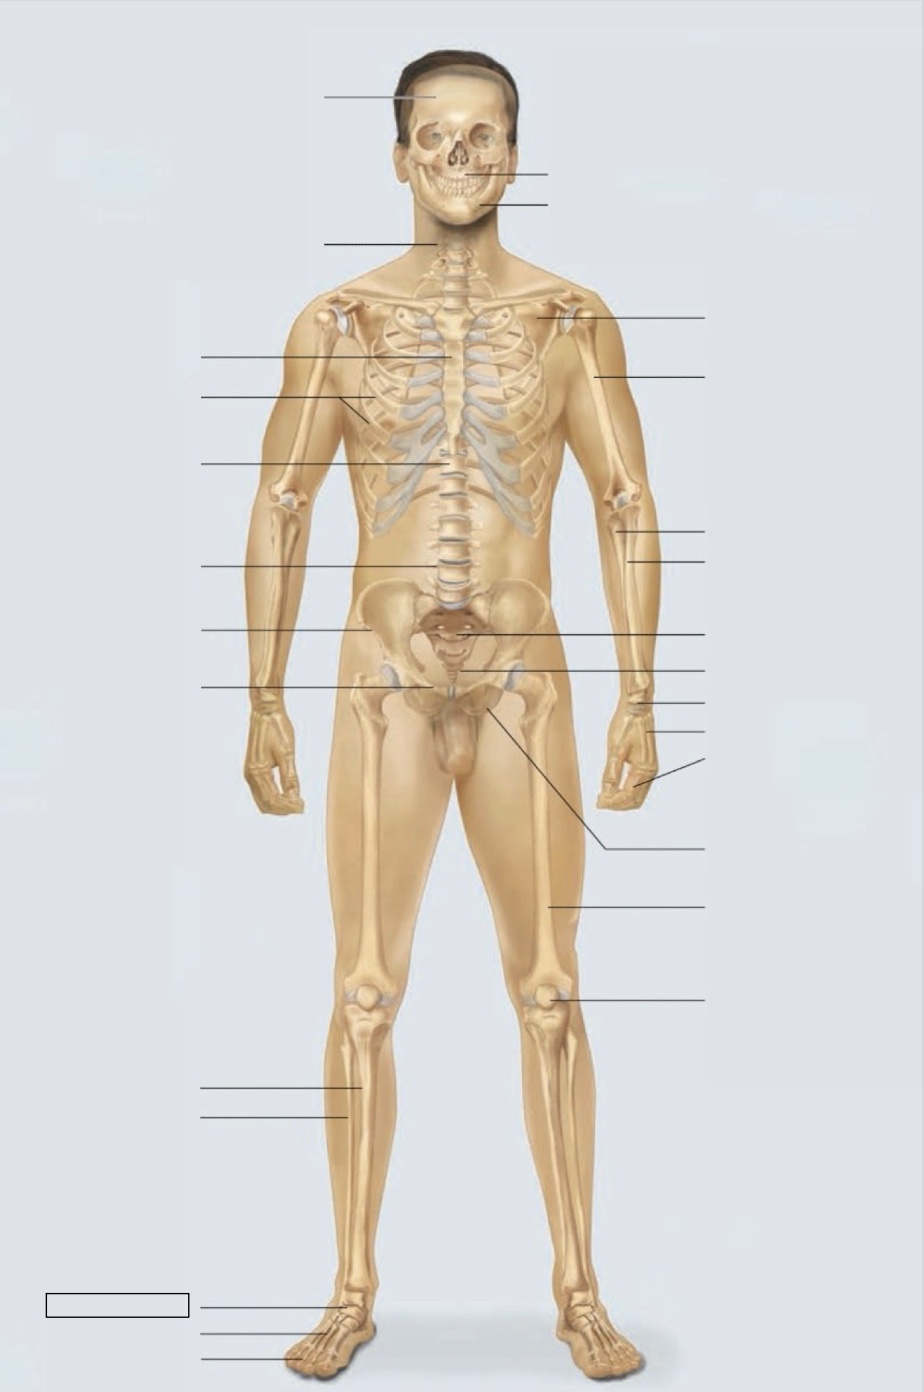

maxilla

mandible

scapula

humerus

ulna

radius

sacrum

coccyx

carpals

metacarpals

phalanges

ischium

femur

patella

phalanges

metatarsals

tarsals

fibula

tibia

pubis

ilium

lumbar vertebrae (L4)

thoracic vertebrae (T11)

ribs

sternum

cervical vertebrae

skull